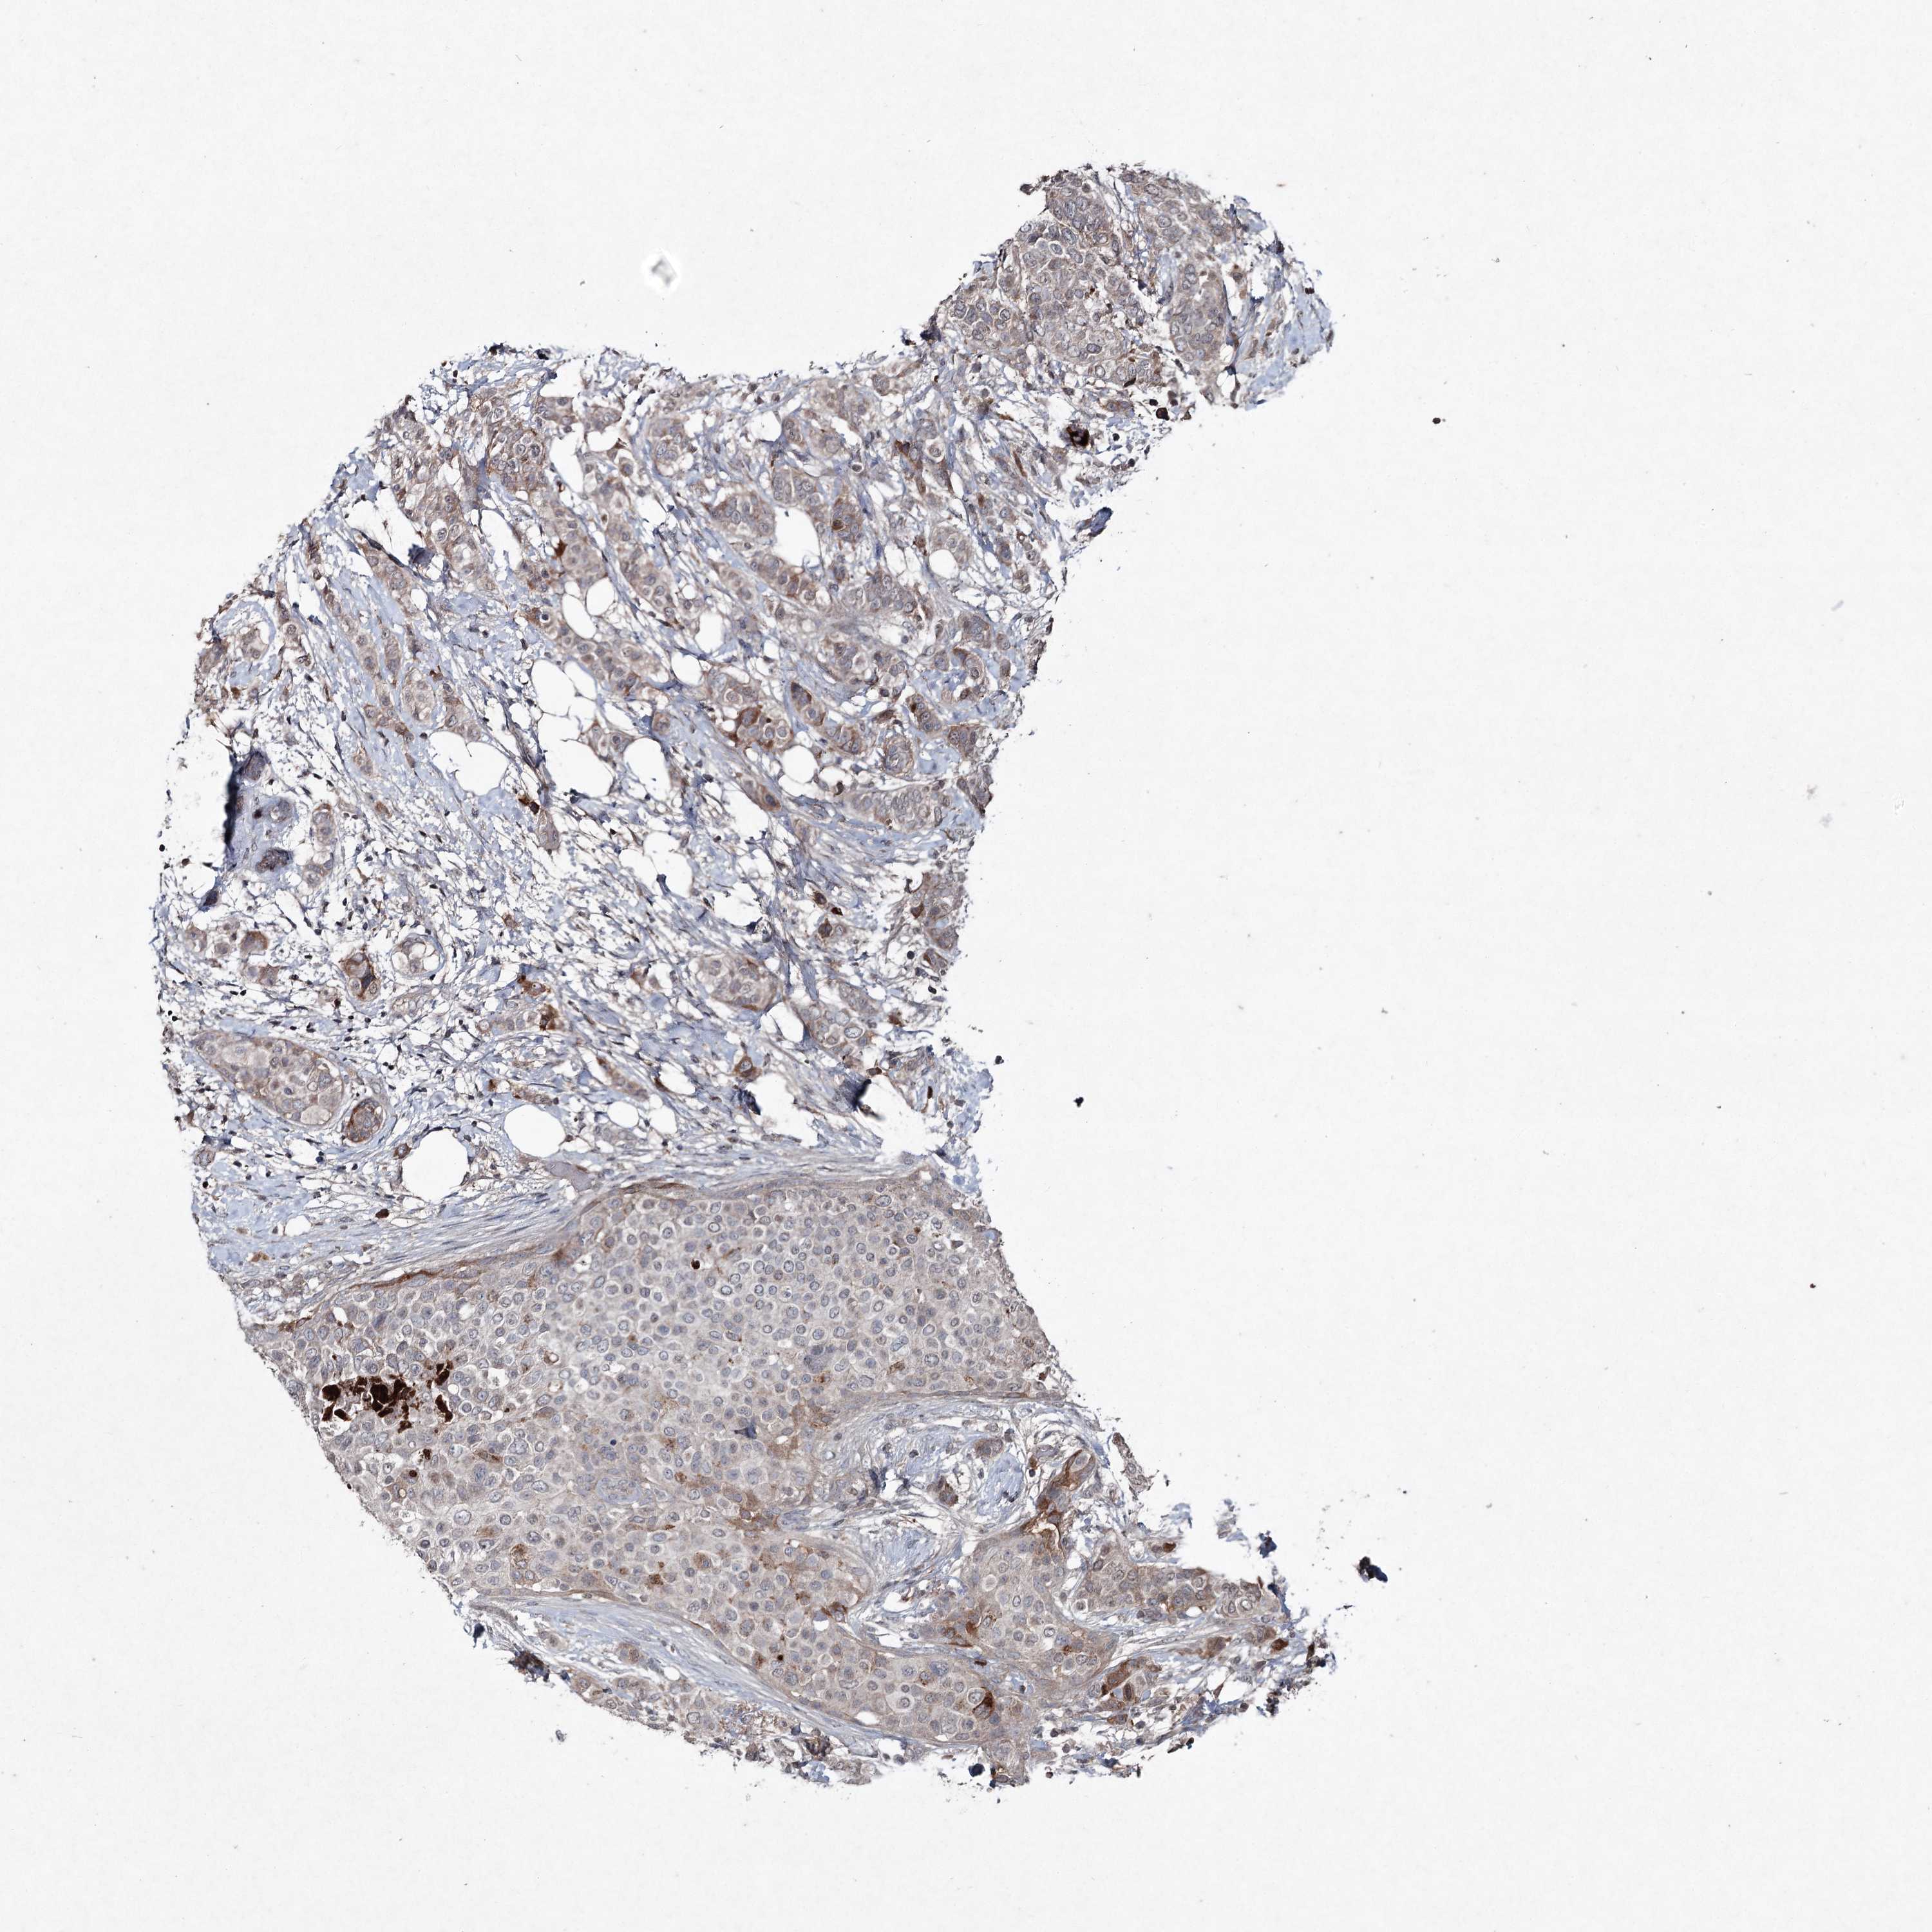

BRCA TCGA BRCA VALIDATION PROTEIN EXPRESSION

ANTIBODIES

AND

VALIDATION